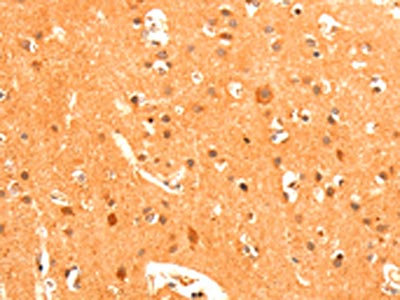

The image on the left is immunohistochemistry of paraffin-embedded Human brain tissue using CSB-PA449040(GRM3 Antibody) at dilution 1/50, on the right is treated with fusion protein. (Original magnification: ×200)